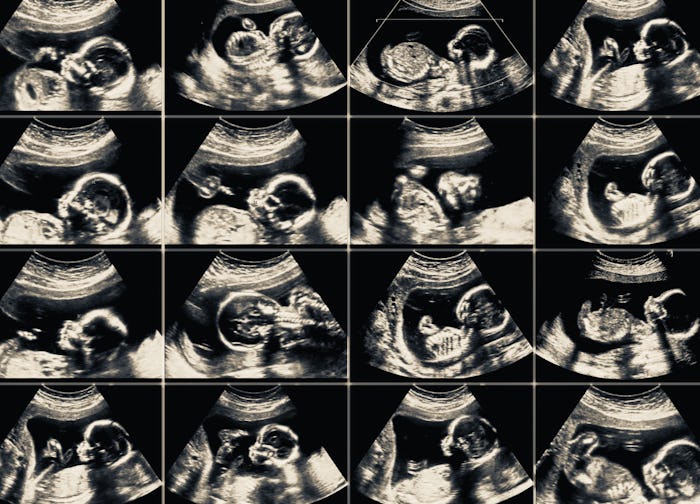

Two hospitals in the U.K. are introducing a way to memorialize the babies lost to women in early pregnancy: ultrasound photograph keepsakes. Kevin Phillips, the hospitals’ chief medical officer, stated, “We understand and appreciate how difficult it is to lose a child, regardless of when that occurs in a pregnancy.” He acknowledges that not all women may be in the state to want a photo, but the option is there if they feel they might want it.

What these two hospitals in Europe are doing is showing that all women who had a miscarriage deserve to have their babies remembered. What they put into motion is something we in the U.S. need for women like me: those who grieve a baby that was so small they may not even show up well on a ultrasound. Having that single picture of my child is all I have to prove that they existed in me. It’s how I keep my baby alive. I would have loved to have an ultrasound and see my sweet babies at whatever stage their little earthly bodies had developed to. It would make the loss less of a private grief. There are funerals to help families grieve the loss of loved ones, but no real ceremonies that help families grieve the loss of early pregnancies. Even just acknowledging that this loss is real would be a step in the right direction.

My babies mattered. They have names. I have tattoos for them. They’re a part of me and my life story and if someone were to offer to remember them by taking a picture for me it would have meant the world. We will never get to look into our babies eyes or watch them grow. But having that moment frozen in time — to most moms that would be irreplaceable.